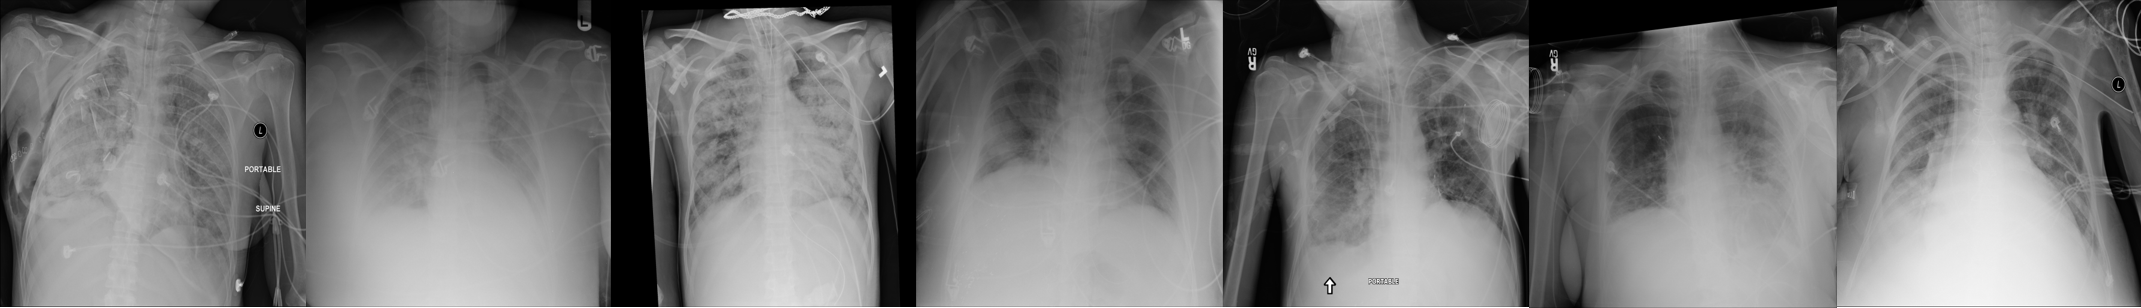

Refer to caption

Figure 1: Examples from the NIH public dataset [6]

In this study, we apply a technique to insert synthetic ET tubes as an overlay to the original X-ray images taken from a publicly available dataset of chest radiographs [6] (hereon will be called the NIH dataset). This dataset contains over 100,000 frontal view images, many of them coming from ICU patients. While annotations are provided for 14 lung diseases, no annotations exist for the presence of ET tubes (or other tubes). A few sample images from the NIH dataset are shown in Figure 1 - the cases have high variability and many have poor image quality. We only used cases in Anterior-Posterior (AP) positioning to simulate intubated patients.